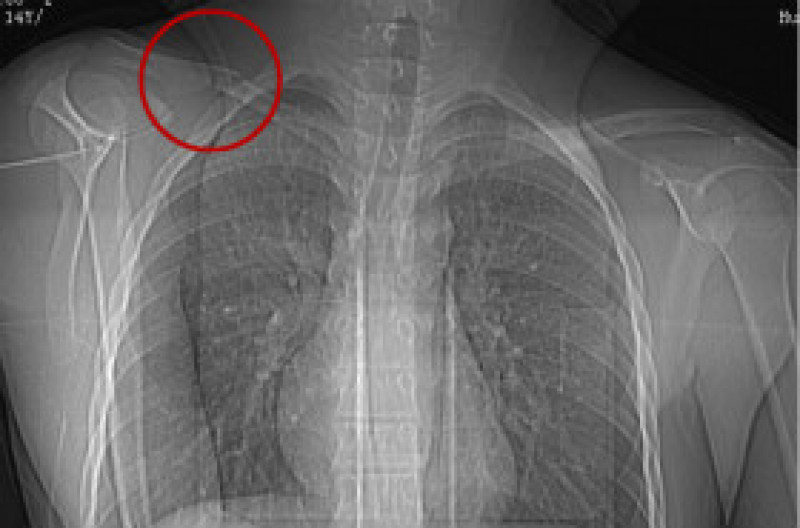

入院后进一步检查发现,小陈左侧鼻腔被肿瘤占据,鼻中隔向右侧鼻腔推挤。与该院神经外科、放射科、麻醉科、手术室等多学科专家会诊讨论并完善术前准备后,7月3日,在该院耳鼻咽喉头颈外科主任肖旭平和神经外科主任舒毓高的指导下,手术团队采用经鼻内镜和显微镜联合入路,成功切除小陈鼻腔鼻窦及颅底巨大肿瘤,切下的肿瘤约8厘米×7厘米×6厘米,重约280克。术后,小陈左眼溢泪停止,外凸的眼球基本回缩,肿大的鼻面部恢复正常,视力也较之前好转,于7月22日康复出院。